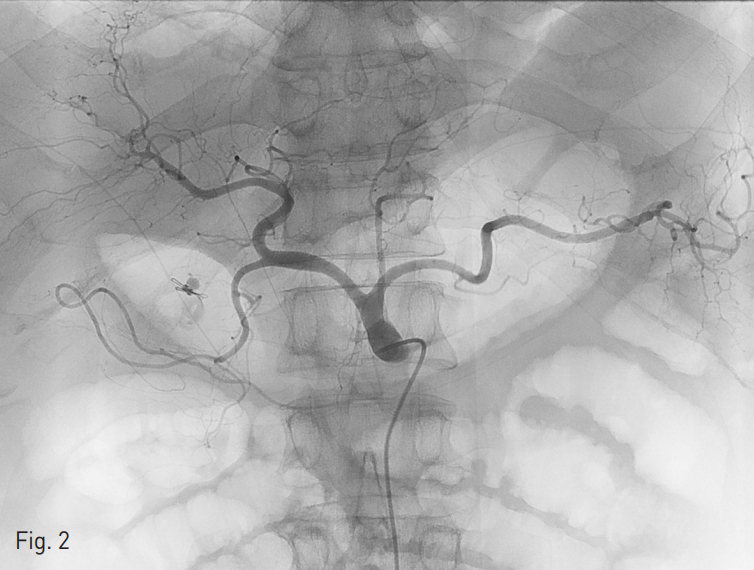

오른쪽 총대퇴동맥을 천자하여 5Fr sheath를 삽입하였다. 이후 4 Fr Yashiro catheter (Jung Sung Corp., Seoul, Korea)를 이용하여 복강동맥 (Celiac artery, Fig. 2) 과 위샘창자동맥 (Gastroduodenal artery) 혈관조영술을 시행하였으며 내시경 클립 주변으로 보이는 샘창자상부동맥 (supraduodenal artery)분지에서 가성동맥류를 동반한 혈관외 유출이 확인되었다 (Fig. 3).

Fig. 2

Celiac ar teriography shows ex travasation from the branch of the gastroduodenal artery.